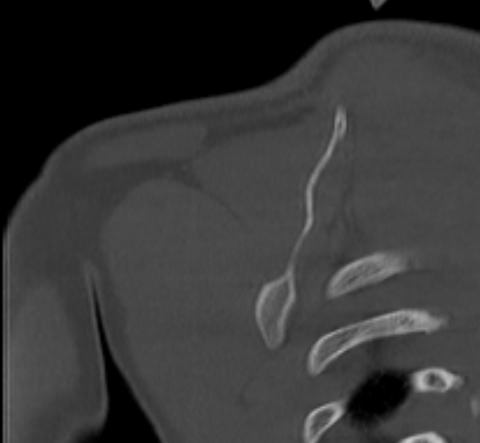

Наиболее информативным методом диагностики патологии плече-лопаточной области является мультиспиральная компьютерная томография. КТ относится к лучевым методам исследования, то есть для получения изображения внутренних органов применяется рентгеновское излучение, которое лучше всего подходит для изучения плотных структур, в частности, костных тканей. В процессе исследования томограф послойно сканирует область лопатки при помощи проникающей способности рентгеновских лучей, затем с помощью компьютерных приложений данные преобразуются в наглядные трехмерные изображения исследуемых органов.

Аппараты сканируют область исследования в течение нескольких секунд, производя одномоментно от 64 до 128 тончайших срезов толщиной от 0,5 мм. Высокая скорость сканирования обеспечивает минимальную дозу облучения для пациента. При этом получаются четкие изображения с высоким контрастным разрешением, что дает возможность рассмотреть исследуемую зону в мельчайших подробностях. Кроме того, томографы создают объемные 3D-изображения области лопатки и прилегающих органов и тканей, что помогает в оценке пространственного соотношения анатомических структур, выявленной патологии и способствует проведению точной диагностики.